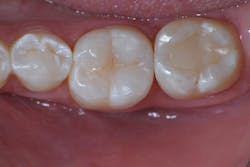

In this case, lateral access was achieved by the preparation of the adjacent teeth as part of the proposed treatment plan. Early caries lesions that are noted on radiographs that are not accessible in cases such as this one can be accessed by placing an orthodontic spacer. This patient was restored with direct composite bonding (figure 5) and these restorations have proven to have a favorable long-term outcome (figure 6).

This patient did not have the burden of the cost, or the loss of precious tooth structure during invasive procedures, including crown lengthening and full coverage restorations. This was economically and emotionally favorable for the patient. He opted to have his early caries lesions treated with resin infiltration during this procedure, which created a more productive dental appointment while promoting more favorable long-term health.